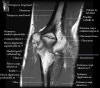

팔꿈치 관절의 MRI 단면 영상

2. Axial section

1) The tendons of the Biceps Brachii and Brachiallis muscles transversely as they insert onto the Radius and Ulna respectively. 2) The distal Triceps tendon is also well evlauated in this plane.